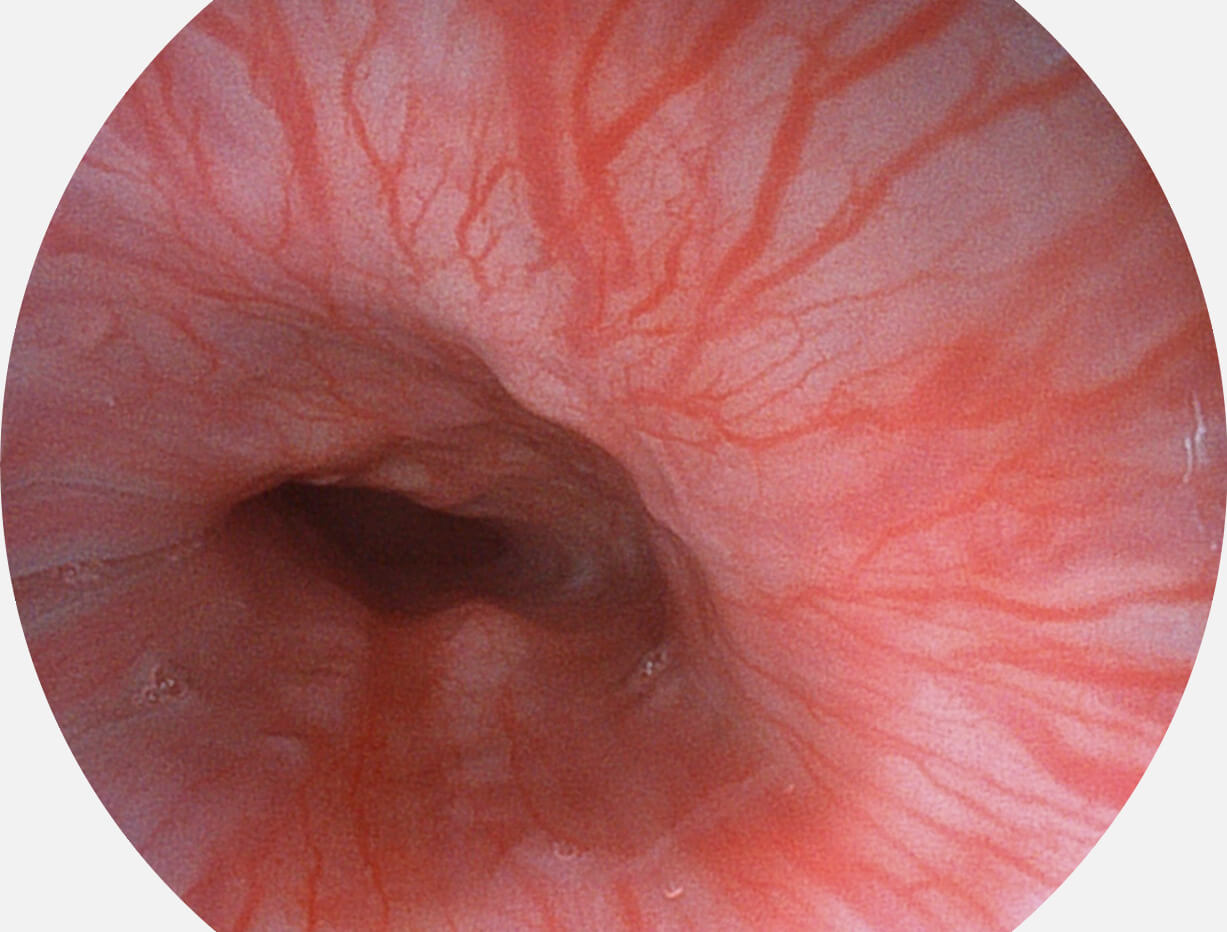

白光图像

SFI图像

VIST图像